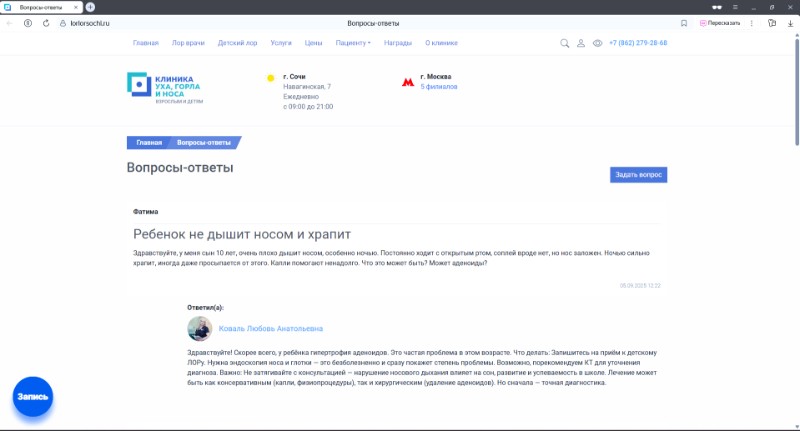

11.11.2025У нас отличные новости! На сайте «Клиники уха, горла и носа» в Сочи открылся новый раздел «Вопросы-ответы», где каждый может получить профессиональную консультацию от наших ЛОР-специалистов.

11.11.2025У нас отличные новости! На сайте «Клиники уха, горла и носа» в Сочи открылся новый раздел «Вопросы-ответы», где каждый может получить профессиональную консультацию от наших ЛОР-специалистов. -